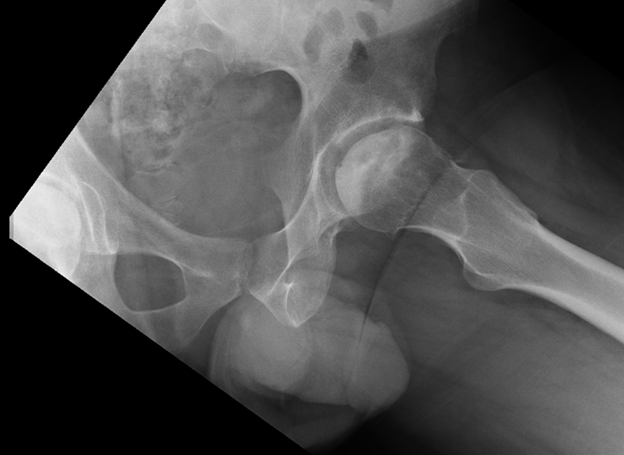

Pelvis/Hip Case 1 Diagnosis

Avascular Necrosis of the Femoral Head

Plain radiographs may be unremarkable in the early stages of AVN (stage I) or show osteopenia.

In mild disease (stage II), plain films may show a mixed picture of osteopenia and sclerosis and may also have subchondral cysts. The femoral head maintains its normal contour (as in the patient in this case).